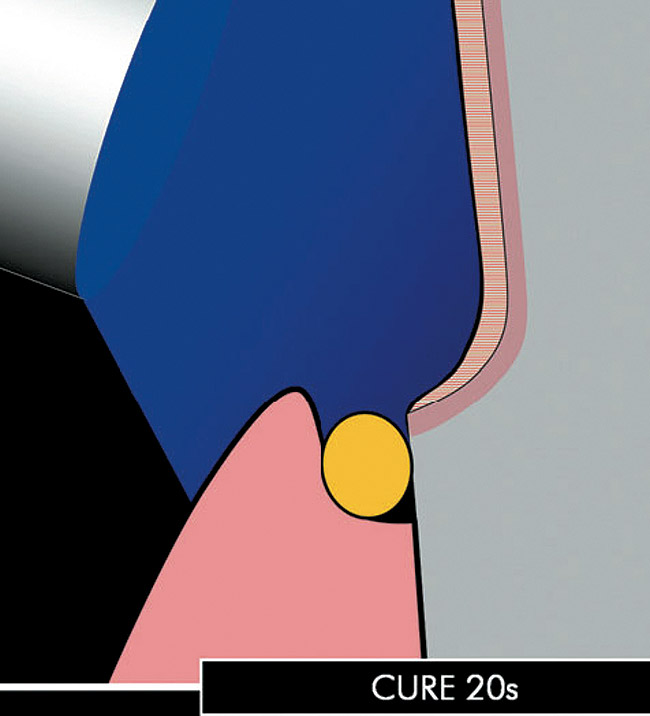

After a first curing (regular mode 20 seconds [Figure 2O and 2P), a layer of glycerin jelly (air block) is applied to the adhesive and slightly beyond. Additional curing (regular mode 10 seconds) of the DBA through a layer of glycerin jelly is recommended (Figure 2Q) to polymerize the oxygen inhibition layer and prevent interaction of the dentin adhesive with the impression material (especially polyethers). Accurate placement of the adhesive resin is usually confirmed by the removal of the deflection cord as the latter should not adhere to the margin (Figures 2R and 2S).

Figure 2o  The adhesive can be cured  for an initial 20 seconds.

Figure 2o

Figure 2p  The adhesive can be cured  for an initial 20 seconds.

Figure 2p